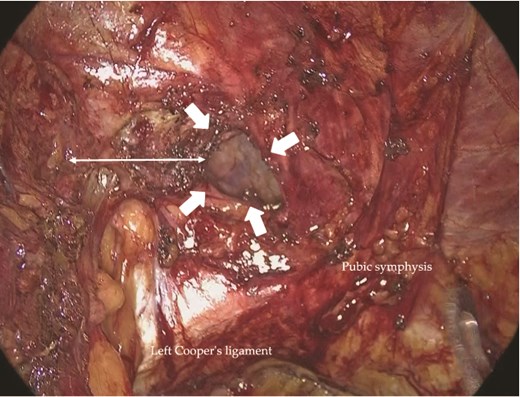

On the left, the recurrent hernia orifice was identified adjacent to one of the mesh plugs, with the pseudosac firmly adherent to the plug (Fig. 5). After careful sharp and blunt dissection, a recurrent orifice was clearly exposed in the left pubic region and classified as R1M2 (Fig. 6). A circumferential margin of ~2.5 cm was secured around the defect. The laterally placed plug did not interfere with the repair and was left in situ. A 15 × 10 cm self-gripping mesh (ProGrip™) was placed to cover the recurrent defect with a 2.5 cm margin and was supplemented with tacker fixation because overlap was limited (Fig. 7). Although the left-sided mesh covered the right hernia orifice, overlap on the right was insufficient (Fig. 8), so an additional mesh was applied for reinforcement. The right-sided high peritoneal incision was sutured and closed in a standard fashion (Fig. 9). The postoperative course was uneventful. At 5-month follow-up, there was no clinical evidence of recurrence.

Adhesions between the previously placed mesh (arrows) and the peritoneum in the left inguinal region.

Intraoperative view of the left inguinal region. An R1M2-type recurrent hernia orifice (arrows) was identified adjacent to a mesh plug. A circumferential margin of ~2.5 cm (double-headed arrow) was secured around the defect.